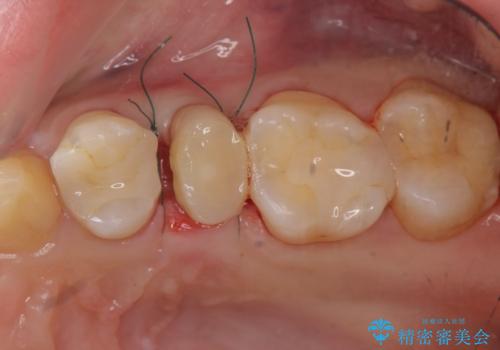

- 部分ワイヤー矯正

当初、歯ぐきよりも深い虫歯のぞんざいや、歯のポジションに問題がありましたがマルチブラケットを用いた部分矯正を行うことで適切な位置へと歯を移動させ、歯周環境を整えたセラミック治療を行うことができました。